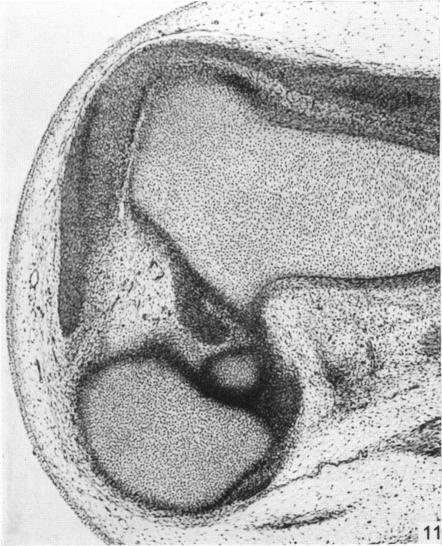

The early development of the knee joint in staged human embryos.

J Anat. 1968 Jan;102(Pt 2):289-99.